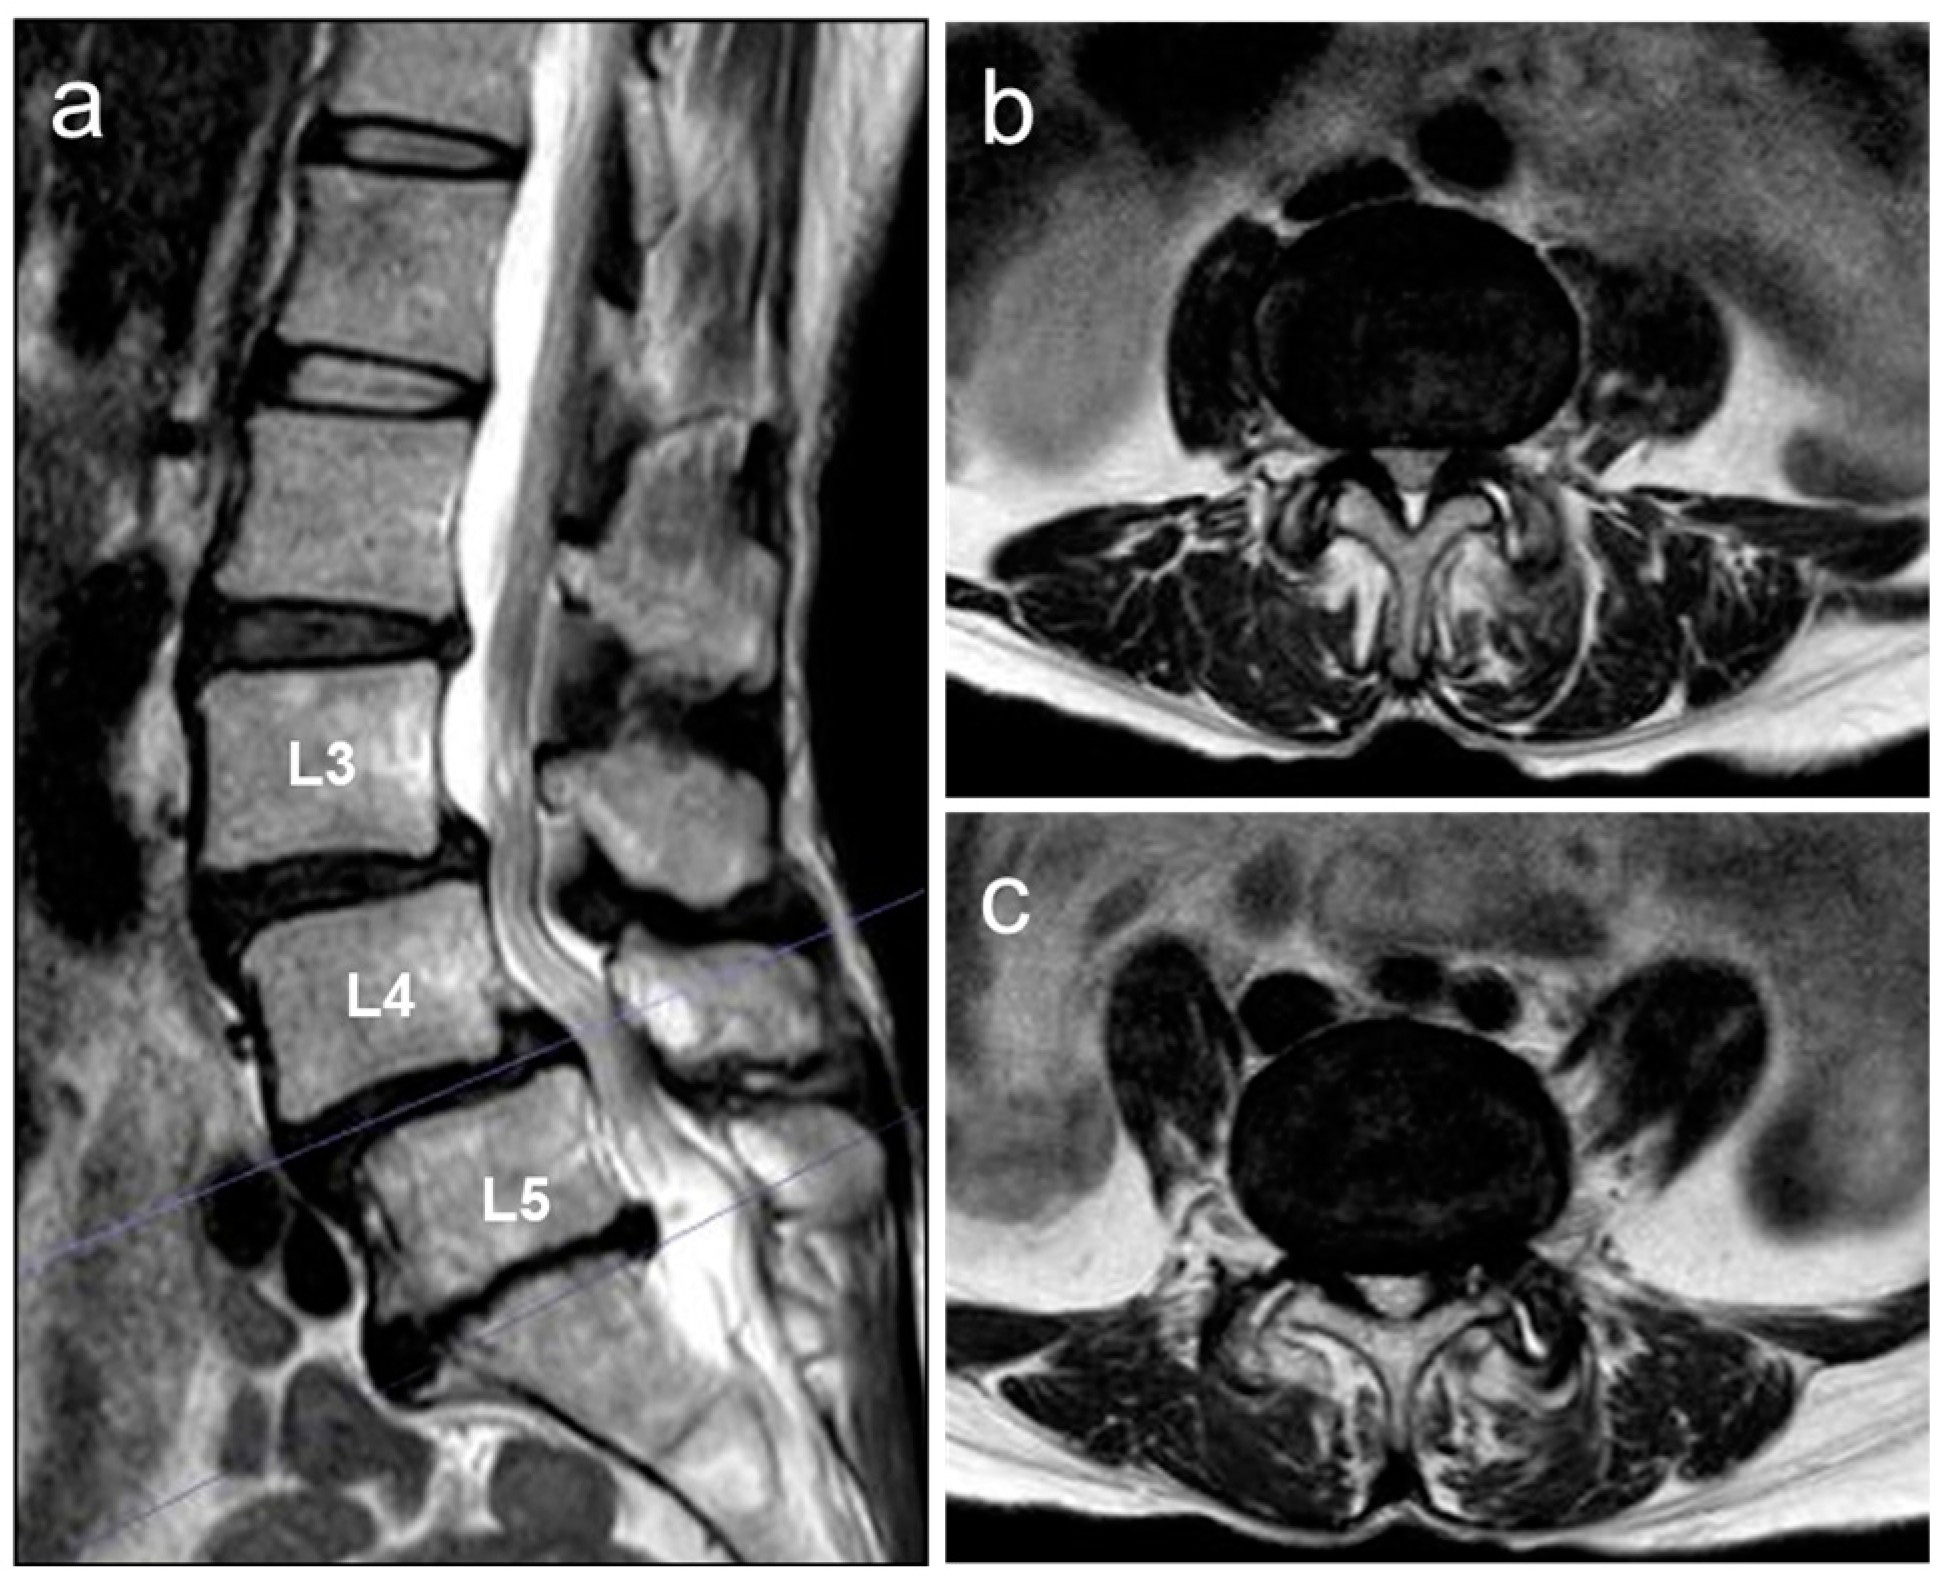

2.4. Image Examinations after Six Months of Daily Physical Exercise